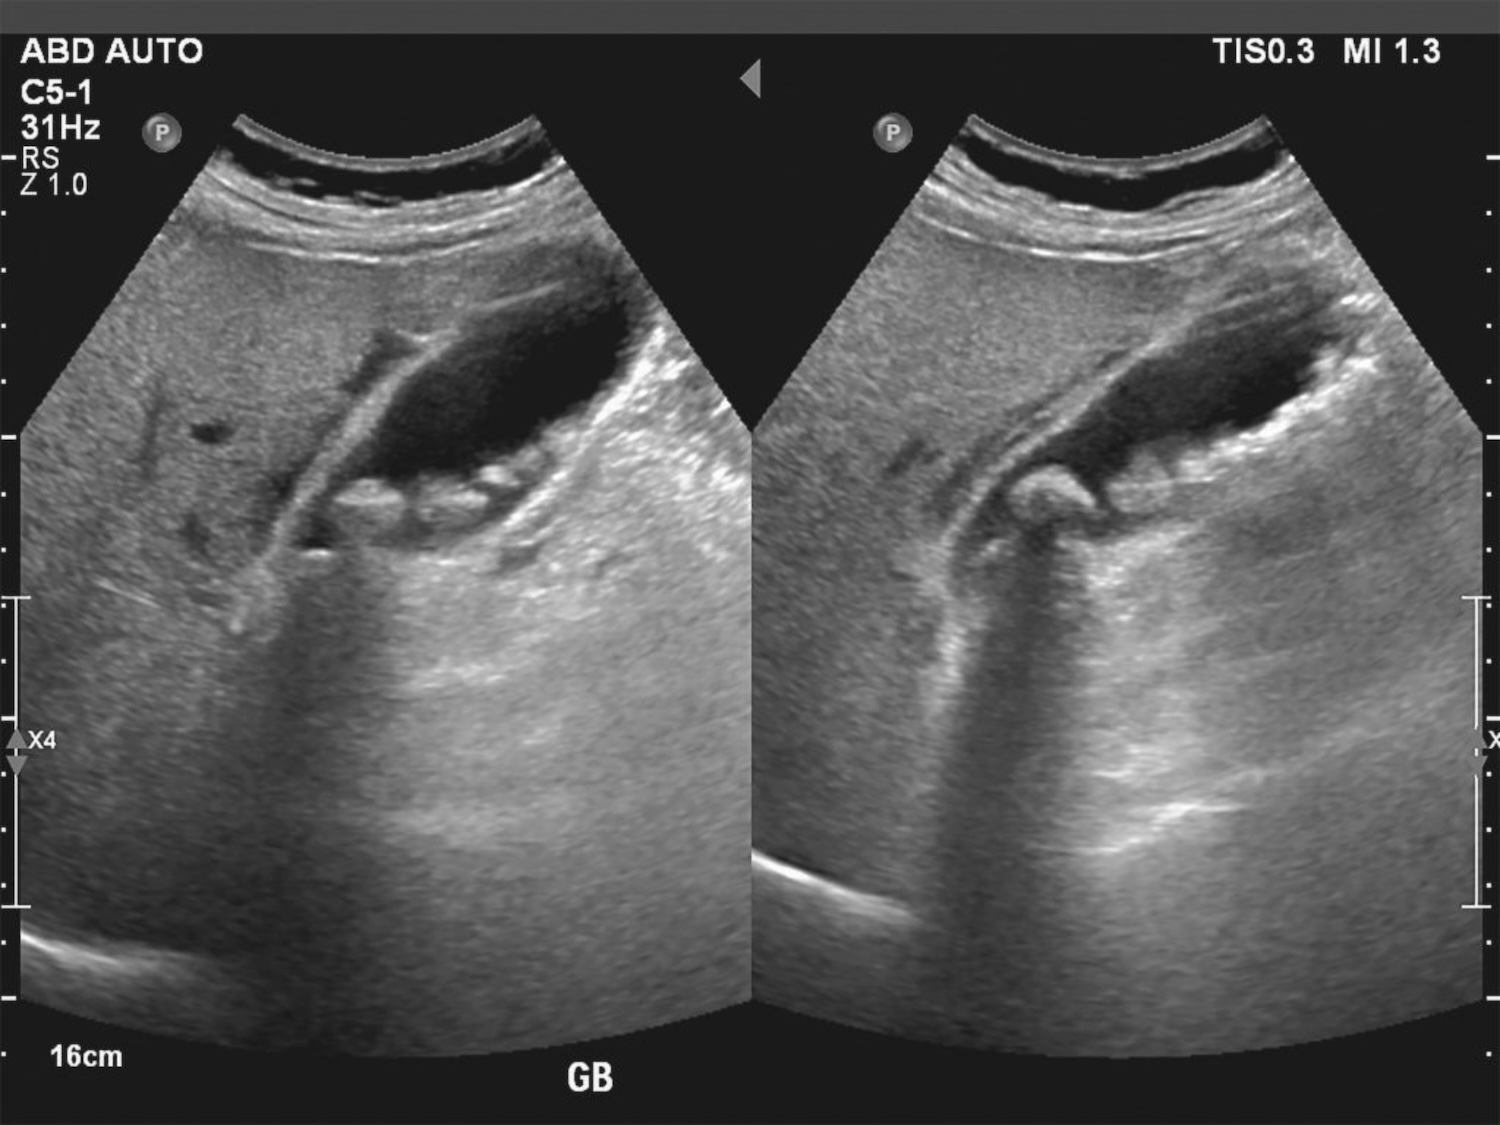

Υπερηχογράφημα Χοληδόχου Κύστης

Το υπερηχογράφημα άνω κοιλίας είναι η εξέταση εκλογής όταν υπάρχει υποψία χολολιθίασης. Είναι η πιο ευαίσθητη, η πιο ειδική και η πιο φτηνή μη επεμβατική εξέταση για τη διάγνωση της νόσου. Επιπροσθέτως, ως εξέταση, είναι απλή, γρήγορη, ανώδυνη, ασφαλής ακόμη και κατά τη διάρκεια της εγκυμοσύνης και δεν εκθέτει τον ασθενή στους κινδύνους της ακτινοβολίας και του ενδοφλέβιου σκιαγραφικού. Η ευαισθησία του υπερηχογραφήματος για την ανεύρεση λίθων > 2mm στον αυλό της χοληδόχου κύστης προσεγγίζει το 99%. Είναι επίσης πολύ υψηλή για τη διάγνωση οξείας χολοκυστίτιδας οπότε συνυπάρχουν πάχυνση του τοιχώματος της χοληδόχου κύστης και οίδημα γύρω από αυτό. Αντιθέτως, για ανατομικούς λόγους, η ευαισθησία της εξέτασης για την ανεύρεση λίθων εντός του χοληδόχου πόρου πέφτει σημαντικά (στο 30-40%) αν και στις περιπτώσεις αυτές ακόμη, μπορεί να συνυπάρχουν κάποια έμμεσα σημεία όπως είναι η διάταση των ενδοηπατικών και των εξωηπατικών χοληφόρων. Η αξονική τομογραφία είναι εξίσου καλή με το υπερηχογράφημα στη διάγνωση της οξείας χολοκυστίτιδας και πιο ευαίσθητη στην απεικόνιση της χοληδοχολιθίασης, αλλά κυρίως χρησιμοποιείται σε περιπτώσεις οξείας κοιλίας για να αποκλεισθούν αίτια από άλλα ενδοκοιλιακά όργανα. Η καλύτερη εξέταση για την αναζήτηση λίθων εντός του χοληδόχου πόρου είναι η μαγνητική χολαγγειο-παγκρεατογραφία (MRCP) η οποία είναι μία παραλλαγή της μαγνητικής τομογραφίας και πρέπει να διενεργείται όταν υπάρχουν κλινικές ή βιοχημικές ή άλλες απεικονιστικές ενδείξεις χοληδοχολιθίασης πριν από την χειρουργική αφαίρεση της χοληδόχου κύστης.